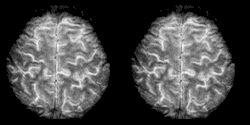

Cognitive neuroscience aims to reduce cognition to its neural basis using new technologies such as fMRI, repetitive transcranial magnetic stimulation (rTMS) and Magnetoencephalography (MEG) as well as older methods such as Positron emission tomography (PET) and Electroencephalography (EEG) studies. Due to the correlational designs used in fMRI, many scientists have coined this up and coming field as the new phrenology in the sense that techniques such as fMRI rely heavily on complex statistics.[17] Type 1 errors can lead scientists to draw premature and incorrect causal relationships if improper designs are used.[18]

Functional magnetic resonance imaging (fMRI) has intriguing implications for the study of memory in humans, however it can also be used in animal models. fMRI can be used to assess brain functionality in monkeys in the context of a variety of behavioral tasks.[26] Structural MRI can be used to examine the extent and location of brain lesions, so that behavioral abnormalities observed can be directly linked to specific brain structures.[27] High-resolution fMRI can help locate and assess the functionality of large neural networks so that these regions can be further studied using more traditional electrophysiological recording devices.[26]